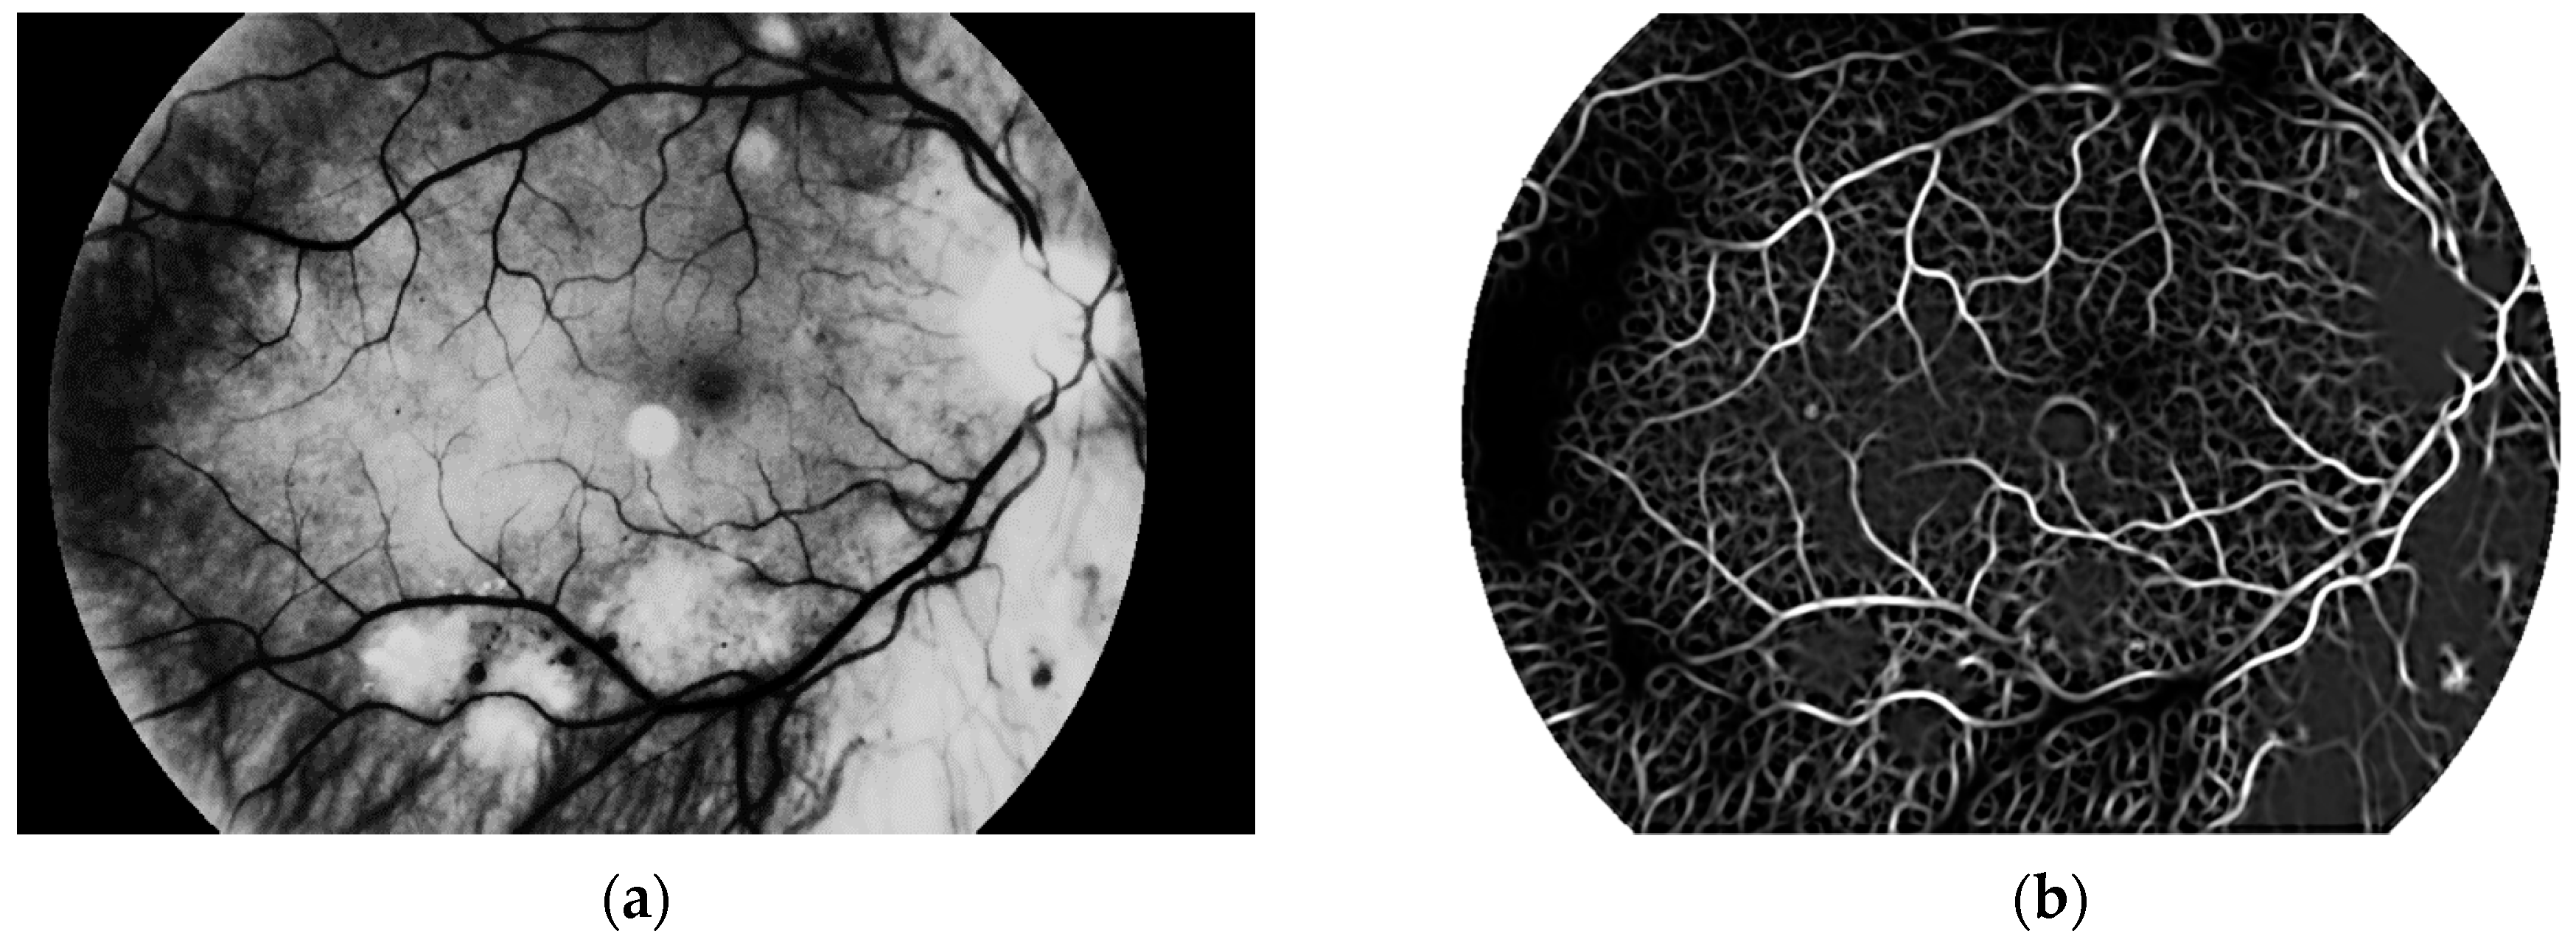

Another step, noise removal, is also done with median filtering. This algorithm is an efficient way to get precise results. Original image and images obtained after both of these steps are presented in Figure 10.

The third and the fourth steps are connected with image enhancement before vessel segmentation. It is done on the basis of histogram equalization (which allows enhancement of the image contrast) and brightness correction. Images obtained after both of these stages are presented in Figure 11.

The main aim of this algorithm is vascular pattern extraction. The next procedure allows segmentation of vessels from the retina image. This is done with a Gaussian matched filter [38]. All twelve masks were used to detect vessels in the retina image. The result is presented in Figure 12.

Figure 10. (a) Original image, (b) image after conversion to grayscale with green channel and (c) image after noise removal.

Sensors 19 00695 g010

Figure 11. Image after (a) histogram equalization and (b) after brightness correction.

Sensors 19 00695 g011

Figure 12. Image after (a) brightness correction and (b) Gaussian matched filter.